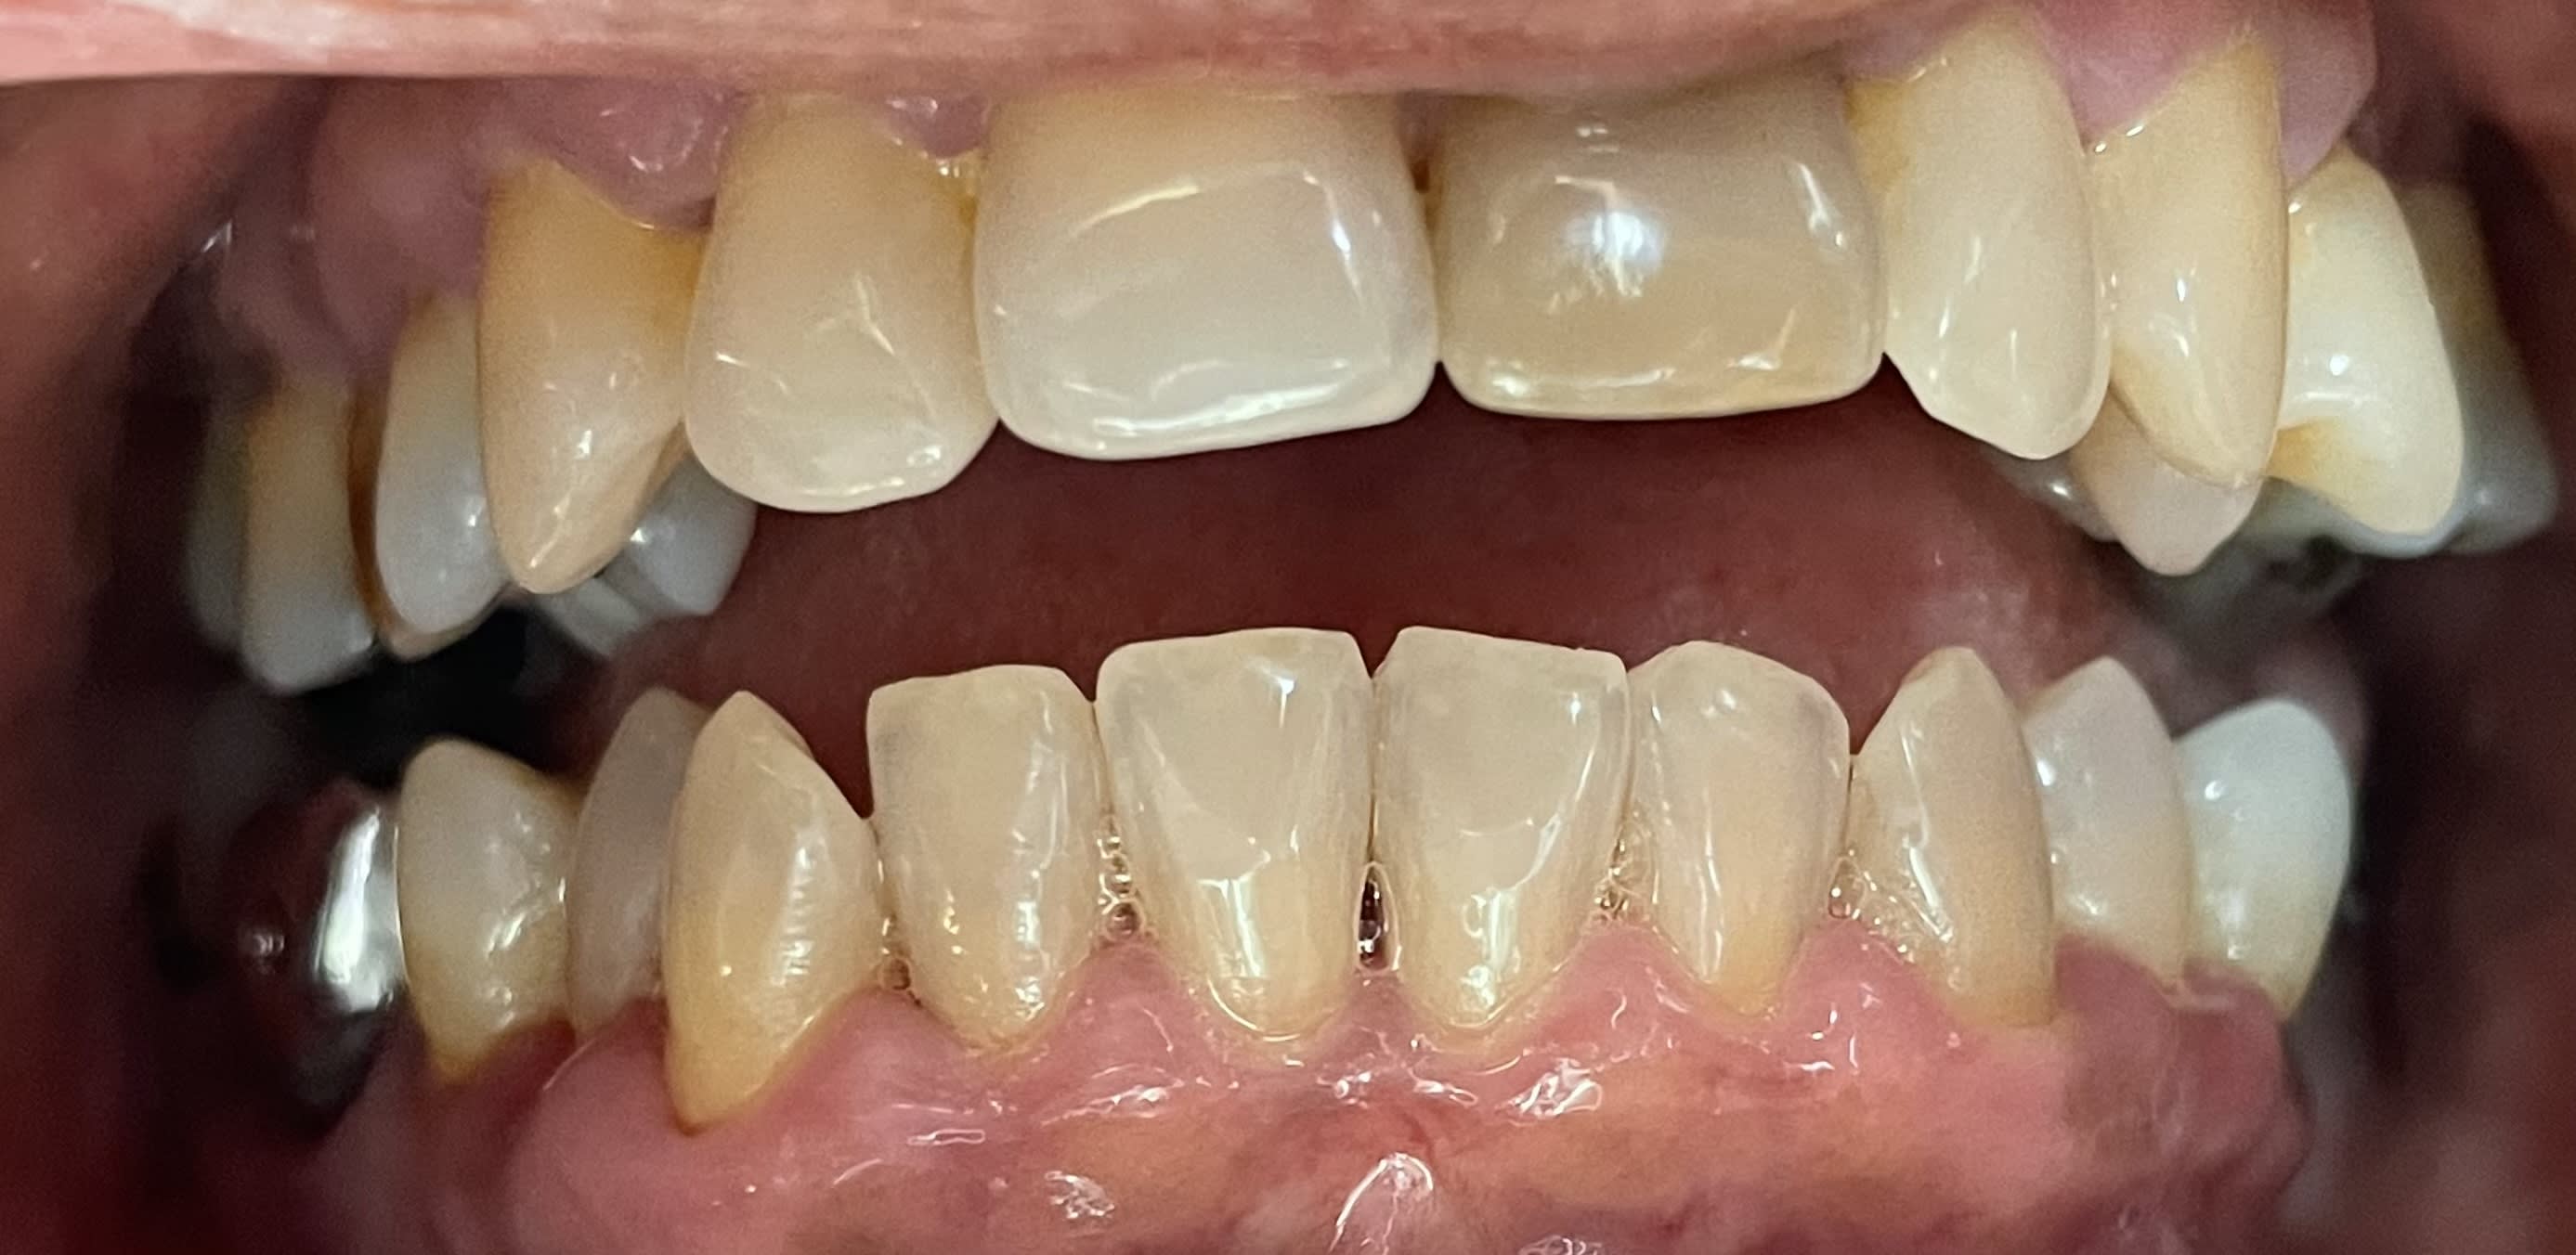

Abeba8c6 3e11 41b8 92b0 67fcd20541e8 eo52uo - Eugenol

41c944f7 8122 4b5e a226 53023e63b627 x9qrwr - Eugenol

Et là elle est en occlusion ? costaud ! Abus de gouttière ??

Port d'une OAM depuis plusieurs années ?

Je n’ai pas compris l’origine du problème. Peut être qu’elle a calé sa langue entre ses dents sauf au niveau des 7...

Ils lui ont viré 36 37 au passage

=> peut-être douleur articulaire avec éventuellement luxation

=> apposition de sa langue pour relâcher la pression

=> et répercussions sur l’occlusion au final

secteur 30 elle est etait genre occlusion croisée , probablement en beance , puis elle a perdu son calage post 36,37 ?

avec en plus une grosse interference 47 ?

tu confirmes ou pas ?

Elle a perdu son calage. Secteur 3 pas certain pour l’occlusion croisée. Et là contact uniquement sur les 7.